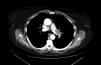

A 68-year-old woman presented with a history of colon and thyroid cancer, and in situ epiglottal carcinoma. In June 2011, fiberoptic bronchoscopy returned a diagnosis of small-cell lung cancer in the anterior segment of the left upper lobe (LUL), for which she received 6 cycles of CDDP-VP-16, and chest and whole-brain radiation therapy (RT). Treatment was completed in November 2011. On radiological studies, a space-occupying lesion was seen in the left pulmonary artery, suggestive of an intramural thrombus (Fig. 1), so anticoagulant treatment was administered for 1 year.

Follow-up radiological studies showed progression of the intra-arterial lesion, suggesting that it might be a tumor. As it was impossible to obtain a sample for histology from this site, surgery was undertaken for the purposes of diagnosis and treatment. Left intrapericardial pneumonectomy with arterial section extending to the disease-free zone was performed. Pathology results confirmed small-cell lung cancer with disease-free surgical margins. No intrathoracic complications occurred during the post-operative period. The patient is currently being followed up by the medical oncologist and has shown no signs of recurrence of her lung disease.